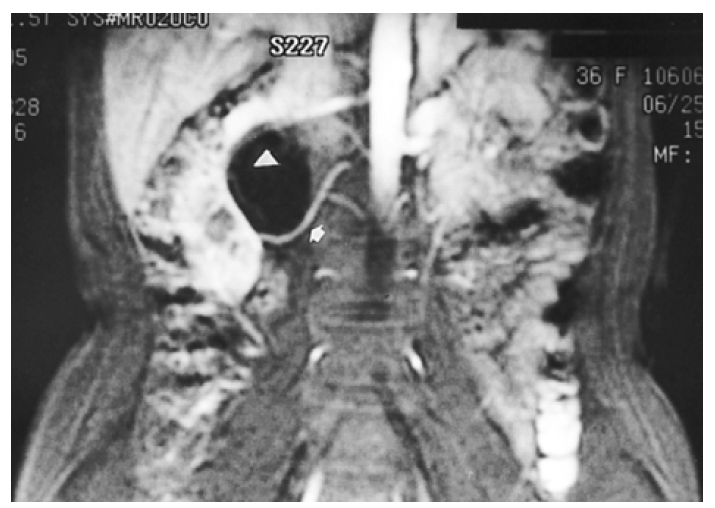

Kidney ultrasonogram showed a marked dilatation of the right pelvocalyceal system and right proximal ureter. However, the left kidney showed normal appearance. Excretory urogram revealed a marked right hydronephrosis with dilated calyces due to ureteropelvic junction obstruction (Figure 1). Computed tomography angiogram (CTA) clearly displayed the aberrant renal artery which originated from the aorta below the normal right renal artery (Figure 2). A source image of magnetic resonance angiogram (MRA) also showed a severe hydronephrosis of the right kidney and smooth obstruction of the right ureteropelvic junction due to extrinsic compression by an aberrant renal artery which originated from the aorta, crossing anteriorly to the ureteropelvic junction (Figure 3). Retrograde pyelogram demonstrated linear indentation of the proximal ureter (Figure 4). Tc-99m DTPA renal scan revealed a markedly delayed excretion of the right kidney. After furosemide infusion, the delayed right kidney excretion was somewhat improved (Figure 5).

Figure 3.

A source image of MR angiogram shows aberrant renal artery (arrow) and extrinsic compression at the right ureteropelvic junction. Dilated pelvocalyceal system (△) is seen with low signal intensity.